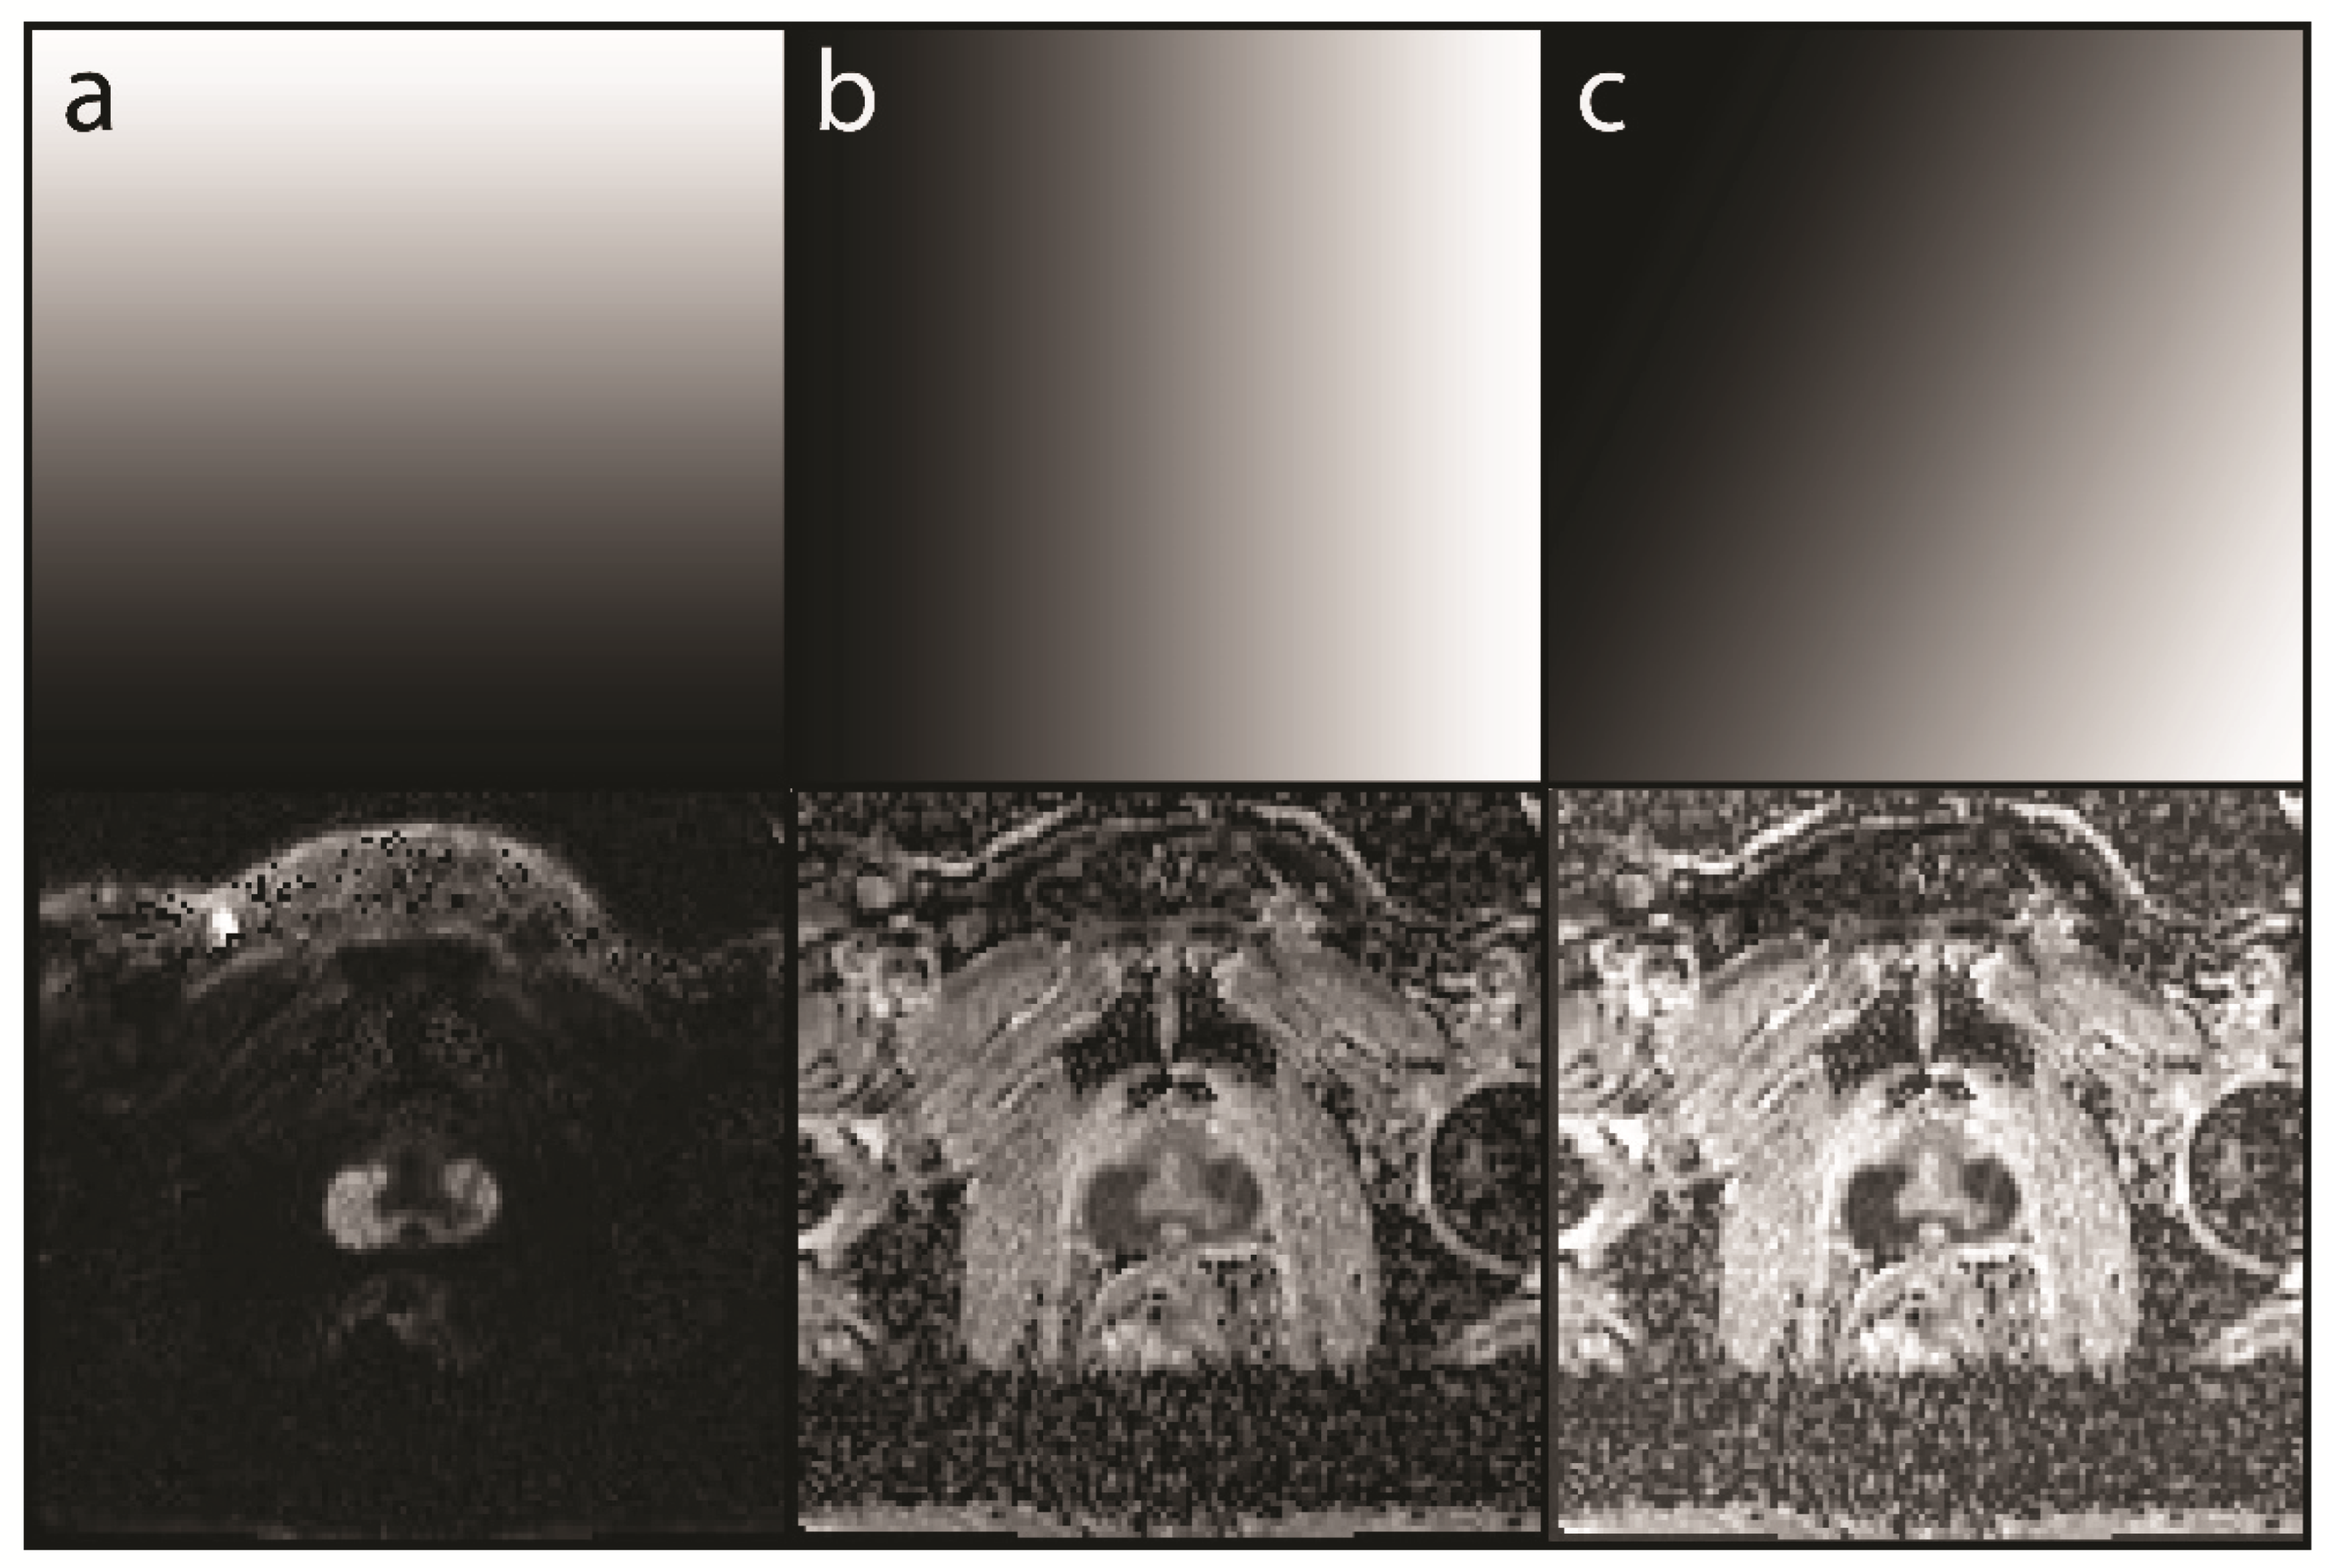

Figure 2. Creation of the map and the mcDI. (a) The ADCs of 70 patients are segmented to create four different 2D histograms (prostate cancer (PCa), red; peripheral zone (PZ), green; transitional zone (TZ), blue; and background (BG), gray). See Figure 1 for further information. It is important to note that the pixel brightness is dictated by the number of voxels plotted into one pixel; the darker the pixel, the more voxels it represents. Due to the exponential representation, every brightness step represents an exponential increase in the voxel density; (b) Fusion: The four 2D histograms are fused to show all the tissues in a single image (for demonstration purposes, a simple image overlay was chosen); (c) Segmentation: The respective areas are segmented into the tumor voxel (PCa) and prostate tissue; (d) Analysis: The segmented areas are analyzed. In concordance with the clinical knowledge, we found that the tumor voxel had an extensive range of DWI and ADC values. However, no tumor was found below a certain DWI threshold, which defined the ‘no-tumor zone’. Furthermore, the conspicuity of the tumor voxels increased with the increasing intensity in the DWI and decreasing intensity in the ADC; (e) Map: These findings were used to create a map that forms the basis of the multichannel computed diffusion images (mcDI). The no-tumor zone was implemented by suppressing the low DWI values. For that purpose, a gradient was used with decreasing brightness correlating to the increasing DWI values. We chose hypo-intensity to represent conspicuous areas, so the resulting mcDI has an ADC-like appearance. However, inverted intensity maps can also be used to generate a more DWI-like image. Since our images exhibit ADC-like characteristics, the main gradient runs vertically from black (ADC = 0) to white (ADC = 1). To include the DWI information, the gradient was tilted clockwise. It is important to notice that the increasing signal in the DWI corresponds to the decreasing intensity in the mcDI; (f) mcDI: The mcDIs are created by reversing the algorithm of the histograms and plotting the intensity of the corresponding location on the map back to the final image. Compared to the ADC, the signal of the fatty tissue and bones is suppressed (lighter), while the tumor tissue is even darker than in the original ADC. The effect on the DWI can be best seen in the reduction of the T2 shine-through.

2.6. Multichannel Computed Diffusion Images

The 2D histograms of these 70 patients (training dataset) were analyzed, and the PCa and normal prostate tissue areas were defined. The size, shape, and location of these areas were used to generate rules for the creation of a so-called intensity map. These rules were translated into gradients that were plotted onto the intensity map. Those rules are explained in detail in the Results. Finally, for each DWI-ADC image pair, a mcDI was generated by plotting the intensity map values back onto the initial voxel locations. For example, tumor voxel A (0.3, 0.2) corresponds to an intensity of 70% gray on the intensity map. Therefore, the voxel in the mcDI will be represented by this dark color. This whole algorithm is visualized in Figure 2. Examples of different readouts are presented in Figure 3.

The analysis of the histograms showed that there is a large overlap in intensity between the PCa and the healthy parenchyma. However, almost no PCa voxel demonstrated a normalized DWI of less than 0.05. This was used to implement a “no-tumor zone” in the intensity maps. Furthermore, the PCa voxels demonstrated a higher normalized DWI value in combination with a lower normalized ADC value. This is in accordance with the clinical knowledge and was therefore also implemented in the intensity maps. The steps of the intensity map creation are part of the algorithm in Figure 2.

In routine clinical practice, a combination of a low and a high b-value is seldom read in isolation. It is standard to calculate an ADC, and in many cases, a higher b-value is calculated to enhance the sensitivity for tumor detection [13,14]. These calculations are, however, purely mathematical and highly standardized; therefore, no knowledge of the underlying tissue is used to enhance the images, especially for a specific study. The present study produced two findings that are commonly known to radiologists but are not yet implemented in image creation. First, tumor conspicuity increases with the increasing signal in hbDWI and decreasing intensity in ADC. We used this characteristic by tilting the axis of the grayscale gradient to combine the information of both images (Figure 3). Second, most of the background has a low signal in the hbDWI, while there are no tumor voxels below a certain threshold. This no-tumor zone was used to reduce the background without losing contrast in the tumor (Figure 4).